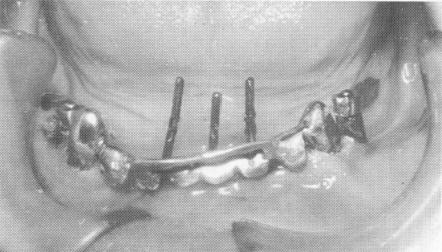

Fig. 13-43. Three pin type implants were then drilled through predetermined holes made in the anterior portion of the template. They were driven as deeply as possible, ending on top of the cortical plate of bone that lay at the inferior border of the mandible.

Fig. 13-44. The excess length of the extending pin implants was cut away so that the pins could be bent underneath the inverted U-shaped bar extending superiorly from the scalloped template.

Fig. 13-45. The pins were then bent so that they fell within the confines of the inverted U-shaped bar.

template (Fig. 13-43). These pins were extended deep into the bone, down to the cortical plate in the inferior portion of the mandible. The three pins were shortened to the height of the horizontal portion of the U-shaped bar (Fig. 13-44) and then bent anteriorly so that they fitted flush to, but underneath, the horizontal bar (Fig. 13-45). The three pins were fused together (using the brush-on technique) and to the entire inverted U-shaped bar with cold cure acrylic, thereby becoming an integral part of the template (Fig. 13-46). An all-acrylicover-gold full arch denture was then processed (Fig. 13-47). The bridge was used as a fixed removable denture and was set buccal to the mylohyoid ridge, instead of on it, to avoid further pain (Fig. 13-48). A Panorex shows the implants and prosthesis (Fig. 13-49) .

1 Three pin implants drilled through holes made in mandibular template

2 Excess length of extending dental pin implants was cut away

3 Pins bent underneath inverted U shaped bar of mandibular template